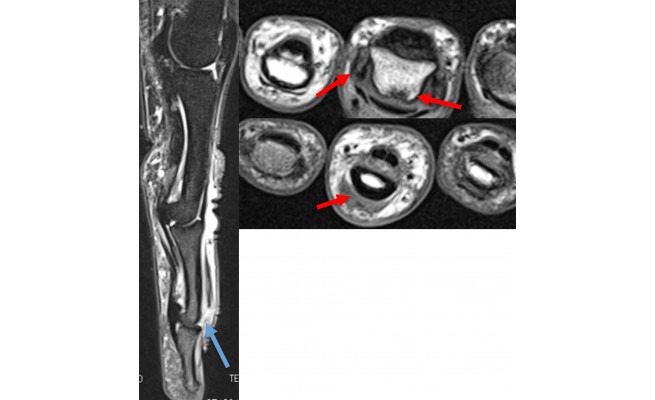

Les lésions de l'extenseur digital, en regard de l'articulation interphalangienne distale, entraînent une déformation en flexion de la dernière phalange des doigts longs liée à la section (ou à la rupture) de la partie terminale des bandes latérales au niveau de l'articulation interphalangienne distale.